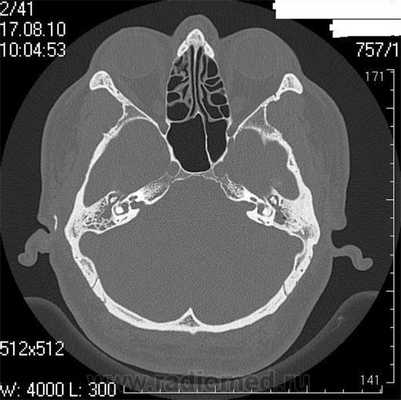

Височная кость является важной анатомической структурой - она участвует в формировании черепной коробки, здесь расположен слуховой аппарат, проходят крупные нервы и артерии. Обычные методы диагностики, такие как рентгенография или УЗИ, зачастую не позволяют диагностировать патологические изменения в этой области. КТ височных костей − более точное исследование, которое дает возможность выявлять заболевания на ранней стадии.

Во время КТ получают послойные снимки височной кости и окружающих тканей в трех плоскостях. Толщина среза составляет всего несколько миллиметров, что позволяет врачу-рентгенологу рассмотреть не только все анатомические образования, но и минимальные патологические изменения.

На полученных снимках хорошо видны следующие структуры:

пирамида височной кости;

ячейки и антрум сосцевидного отростка;

улитка, преддверие, передний и задний полукружный каналы;

слуховые косточки среднего уха;

стенки наружного слухового прохода;

Снимок (томограмма) височных костей в осевой проекции

С помощью КТ височных костей можно выявить любые заболевания воспалительного, травматического, опухолевого характера. Метод применяется для диагностики следующих патологий: